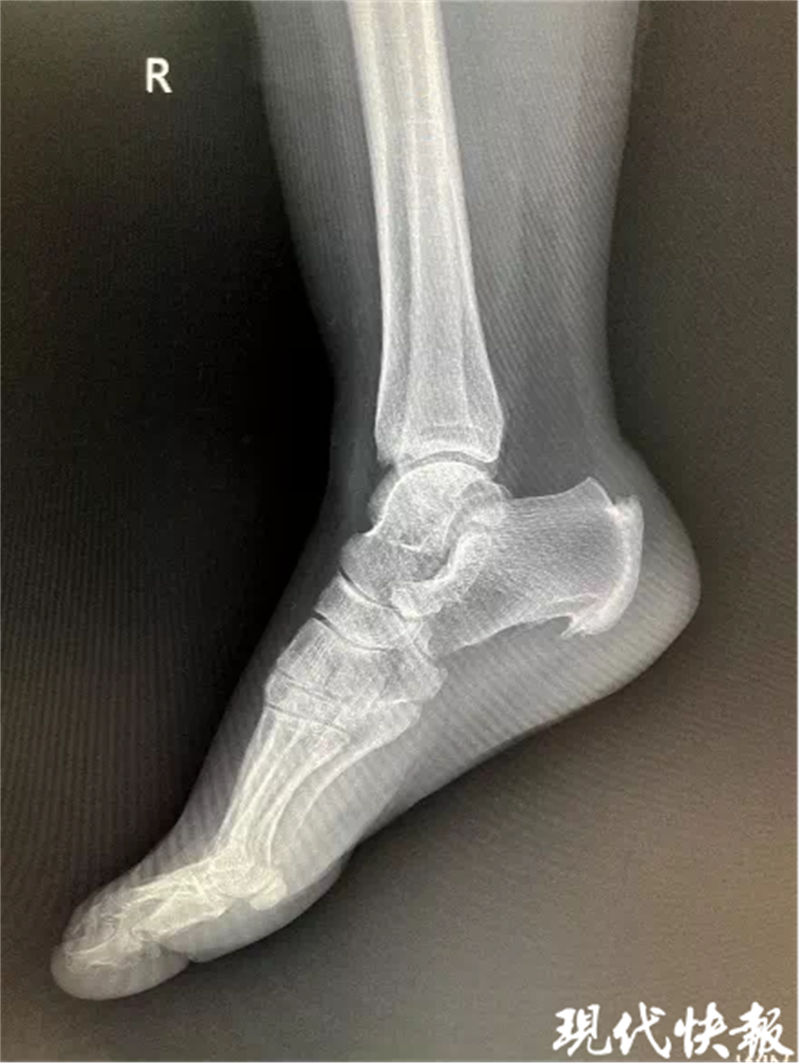

眼看脚后跟鼓出一块“老茧”,天天因疼痛而犯愁,在朋友的推荐下,董女士来到盐城市第三人民医院手足外科门诊咨询就诊。该院手足外科副主任吴加东接诊后发现,董女士的足跟后缘慢性突出,红肿,压痛明显,遂让她去拍了一个跟骨侧位片,发现其跟腱止点处有一个巨大骨赘。

“结合董女士的查体和病史,我考虑她得了Haglund综合征。”吴加东告诉记者,Haglund综合征听起来很陌生,其实在日常生活中并不是十分少见的,1928年,瑞典骨科医师PatrickHaglund首次提出此病,将止点性跟腱炎、跟骨后上突增生(Haglund畸形)与跟腱滑囊炎统称为Haglund综合征。

结合患者病情,在征得本人同意后,吴加东团队为其实施了“骨赘切除+跟腱固定”手术。团队利用微型摆锯将骨赘彻底清除,并将锚钉埋入跟骨内利用尾线将跟腱重新编织缝合,共用时一个多小时。术后,董女士跟骨后上结节异常骨性凸起清除彻底,症状缓解,目前已康复,行走自如。

△患者术前及术后X-ray片